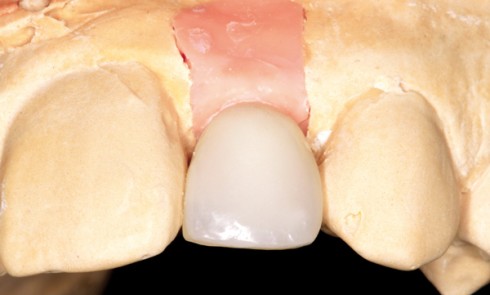

Article réservé à nos abonnés Techniques de transfert du profil d’émergence lors de la confection de la prothèse d’usage

Le profil d’émergence de la couronne est : – créé au laboratoire ou au cabinet lors de la confection de la...